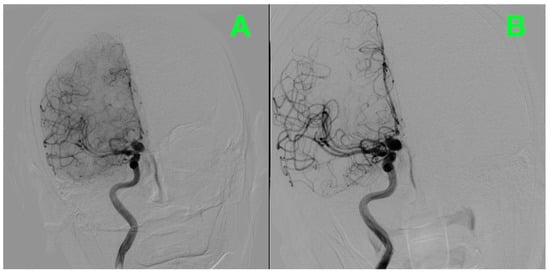

2. Case Presentation